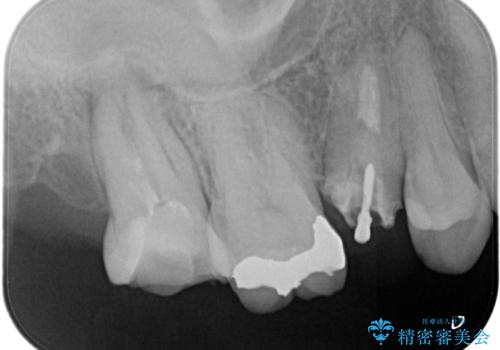

- 左上7番の奥歯に、根尖部の大きな病変を認め来院されました。レントゲンと精密検査の結果、歯の根の先に膿が溜まっている状態と診断。歯を残すことを第一に考え、精密根管治療による改善を目指す治療計画を立案しました。治療においては、細菌の侵入を徹底的に防ぎ、病変部を確実に除去するために、ラバーダムと歯科用顕微鏡を併用することを提案しました。

今回の精密根管治療では、まず治療中に唾液や細菌が入らないようラバーダムで患部を隔離しました。次に、肉眼では見えない根管内部を歯科用顕微鏡で拡大しながら確認。これにより、病変部を正確に特定し、感染源を徹底的に除去することができました。また、健康な歯質を極力残すため、必要以上に歯を削らないよう細心の注意を払って治療を進めました。治療後は、根尖部の病変がきれいになくなり、良好な経過をたどっています。これにより、大切な奥歯を残し、再感染のリスクを抑えることができました。